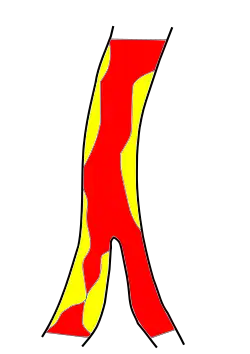

Makroangiopathie

Als Makroangiopathie werden allgemein Veränderungen großer Gefäße bezeichnet. Eine häufige Ursache ischämischer Schlaganfälle ist die Makroangiopathie der großen hirnversorgenden Arterien, die meist durch atherosklerotische Plaques verursacht wird. Durch verschiedene Mechanismen wie Blutdruckanstieg und Infektionen kann es zu einem Aufreißen (einer Ruptur) der Plaques kommen, und es können sich Blutgerinnsel auflagern. Diese lokalen arteriellen Thrombosen können einerseits zu einer Verengung des Gefäßes führen, so dass der zerebrale Blutfluss hinter der Engstelle vermindert ist und eventuell unzureichend für die Versorgung des Hirngewebes ist (siehe den Abschnitt Thrombosen). Andererseits können die lokalen Thromben mit dem Blutstrom mitgerissen werden und damit eine Embolie auslösen. Der Embolus kann dann ein weiter entferntes Blutgefäß verschließen (siehe den Abschnitt Embolien).[3]

Meist sind Thromboembolien für die Entstehung ischämischer Schlaganfälle verantwortlich. Der Embolus stammt dann entweder aus dem Herzen (kardiale Embolie) oder aus den hirnversorgenden Arterien selbst (arterio-arterielle Embolie). Verschiedene Herzerkrankungen wie Vorhofflimmern, Erkrankungen der Herzklappen, akute Herzinfarkte, koronare Herzkrankheit, Herzinsuffizienz und eine Vergrößerung der Herzkammern (ventrikuläre Hypertrophie) erhöhen das Risiko für kardiale Embolien.[5] Zu den kardialen Embolien gehören auch die paradoxen Embolien, die bei Patienten mit venösen Thrombosen und persistierendem Foramen ovale entstehen können.[6] Arterio-arterielle Embolien gehen aus arteriosklerotischen Veränderungen der Arterien hervor. Häufiger Ursprung sind die Aorta, die Karotisgabel und die linke und rechte Halsschlagader.[5]

Thrombosen

Als Thrombosen werden Blutgerinnsel in Gefäßen bezeichnet. Hirninfarkte können durch Thrombosen der hirnversorgenden Arterien ausgelöst werden. Die meisten arteriellen Thrombosen entstehen an solchen Stellen des Gefäßsystems, an denen arteriosklerotischen Veränderungen der Gefäßwand bestehen. Sie können aber auch bei Gefäßverletzungen der Innenseite der Gefäßwand (Tunica intima) entstehen. Dies ist beispielsweise bei Dissektionen der Fall, bei denen es durch einen Einriss der inneren Gefäßwand zu Einblutungen in die Gefäßwand kommt (zwischen Tunica intima und Tunica media). Andere Ursachen für arterielle Thrombosen sind Entzündungen der Gefäßwände (Vaskulitiden) und Gerinnungsstörungen sowie Fremdkörper innerhalb des Gefäßes, beispielsweise Stents und Gefäßprothesen.[3]

Arterielle Thrombosen können langsam oder schnell entstehen. Langsam entstehende Thrombosen sind erst bei hochgradiger Einengung (Stenose) des Gefäßinneren hämodynamisch relevant, das heißt, dass der Blutfluss erst dann nicht mehr für die Versorgung des Hirngewebes ausreicht.[3]